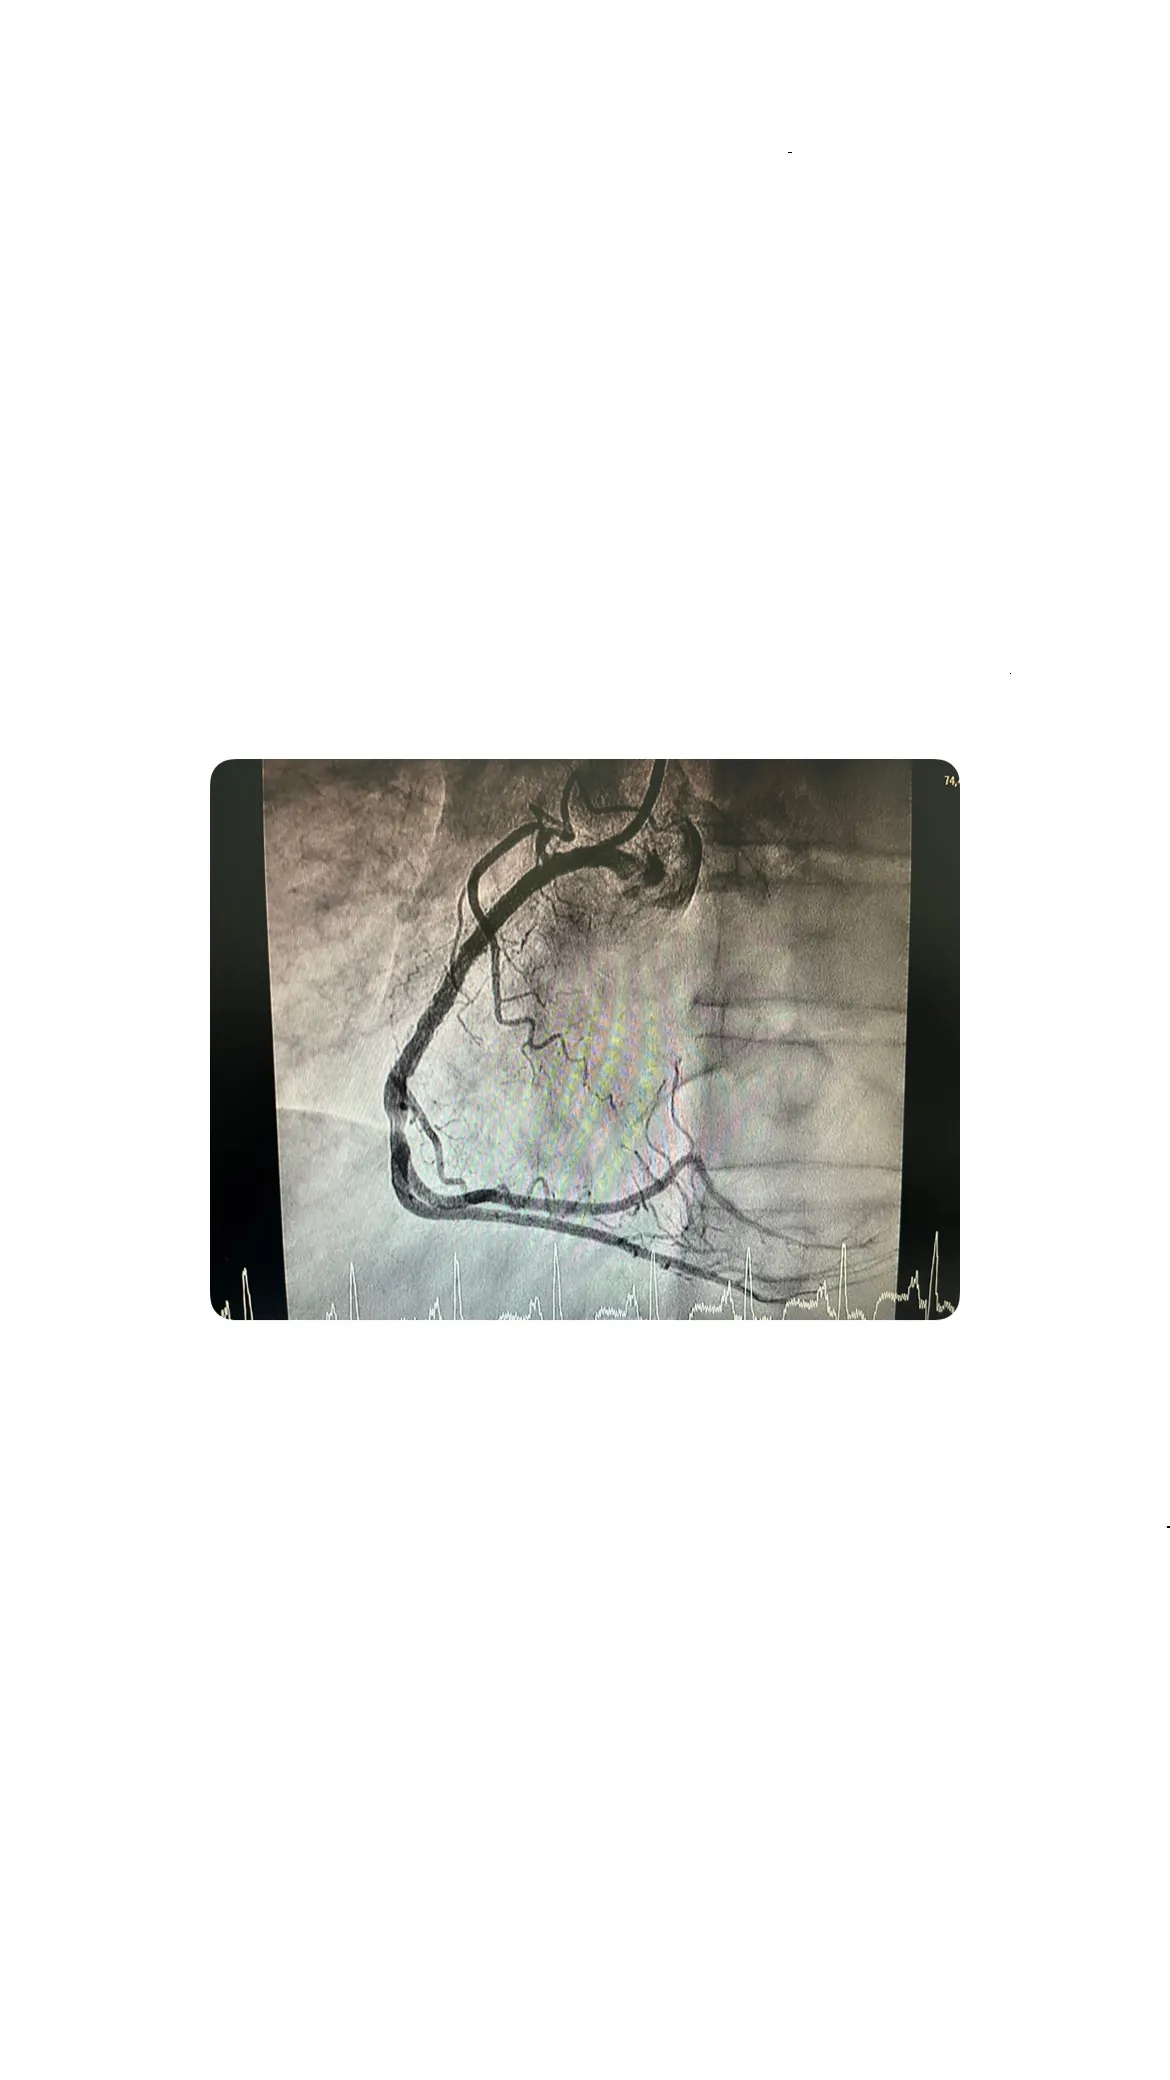

Cateterismo en hemodinámica cardiovascular: hallazgos del caso

Durante el cateterismo realizado en la unidad de hemodinámica cardiovascular, se descubrieron detalles importantes sobre el estado del paciente. Este hombre, procedente de Georgia, ya había sido sometido a la colocación de varios stents. El cateterismo confirmó que tenía un stent permeable en la arteria descendente anterior (DEA) y una reestenosis en el stent de la coronaria derecha.

Confirmación de stent permeable y reestenosis en la coronaria derecha

El cateterismo confirmó que el stent en la DEA estaba permeable, pero se detectó una reestenosis en el stent de la coronaria derecha. Este hallazgo fue fundamental para decidir el tratamiento adecuado y evitar complicaciones mayores en el futuro.